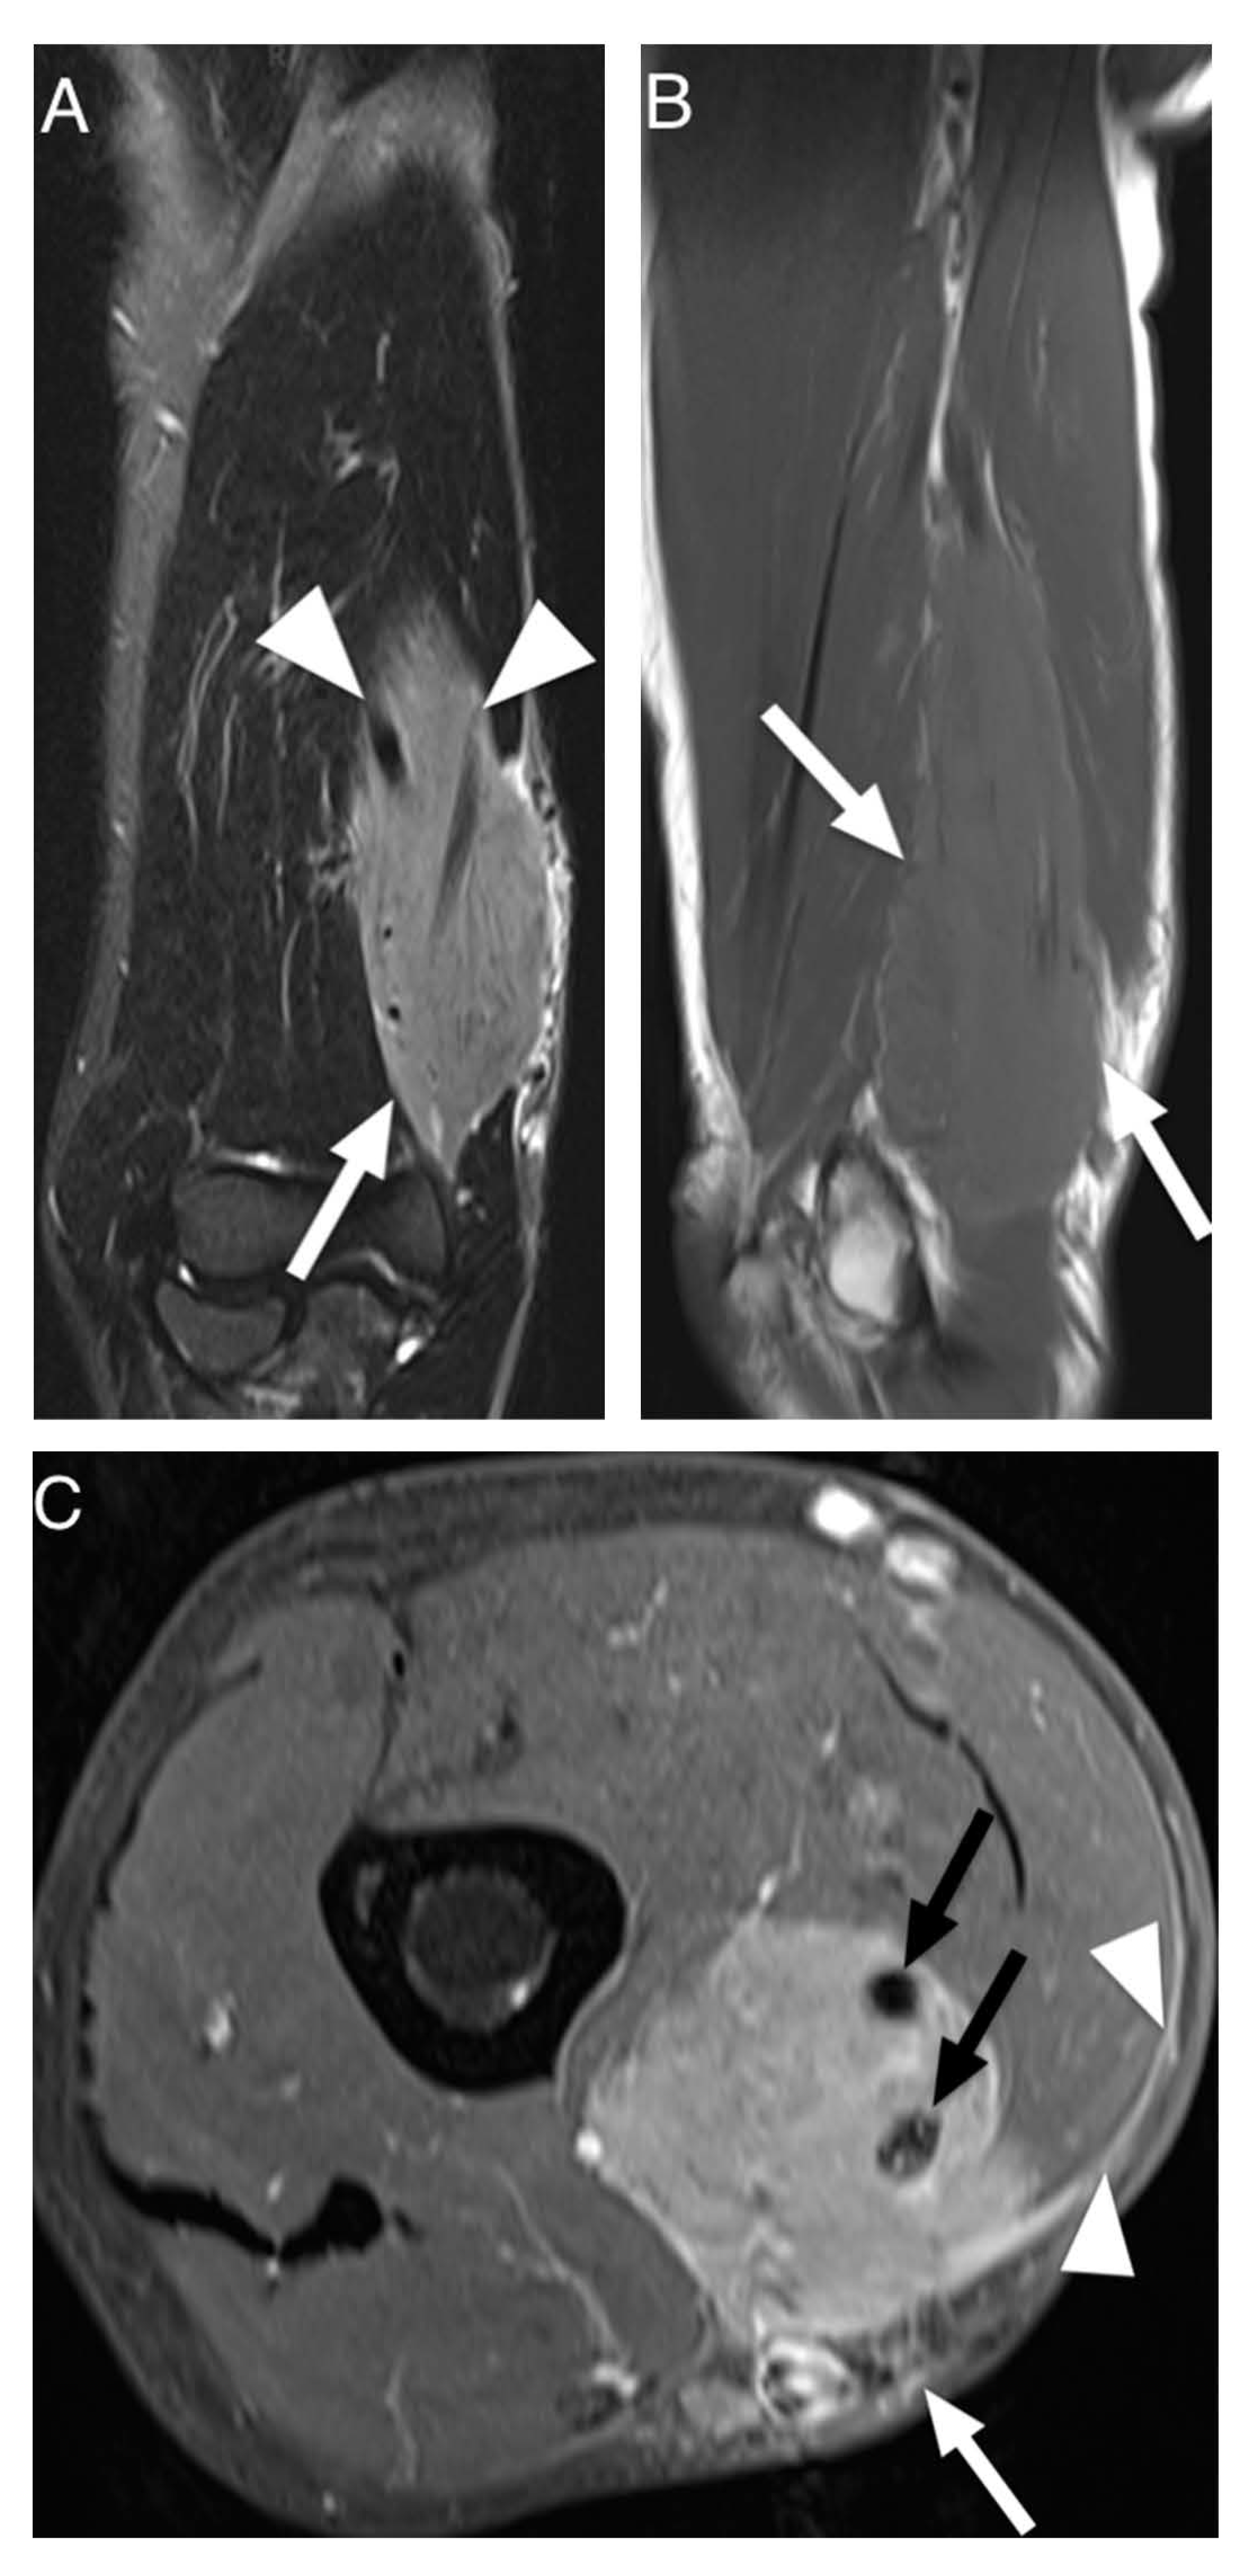

Figure 2.

MRI of a 73-year-old man presenting with non-Hodgkin lymphoma manifestation in the flexor compartment of the upper arm. (A). Coronal T2-weighted TIRM image shows tumor of hyperintense signal intensity compared to muscle (arrow) and growth along the brachial neurovascular bundle (arrowheads). (B). Sagittal T1-weighted image shows long segmental involvement (arrows) and slightly hyperintense signal intensity of tumor in comparison to adjacent skeletal muscle. (C). Transversal contrast enhanced fat-saturated T1-weighted image shows homogenous contrast-enhancement of the lymphoma with encasement of the brachial neurovascular bundle (black arrows). Furthermore, subcutaneous stranding (white arrow) and contrast enhancement of the deep peripheral fascia (arrowheads) can be seen.

Results of extracted MRI data are displayed in Table 4. Signal intensity of lymphoma compared to muscle tissue was mostly described as isointense (53%) or slightly hyperintense (39%) in T1W images and always as hyperintense in T2W images (Figure 2). The majority of T2W images revealed either isointense (47%) or hypointense signal intensity (45%) of lymphoma compared to fat. Hyperintense signal intensity compared to muscle was reported in all PD-weighted (n = 3) and STIR (n = 18) images. In fat-suppressed T2W images, one lesion (5%) showed isointense signal intensity to muscle, nine (43%) lesions showed isointense signal intensity to fat, three (14%) lesions showed intermediate signal intensity between fat and muscle and eight (38%) lesions showed hyperintense signal intensity compared to fat. None of the included articles investigated signal intensity in T1W, PD or STIR images compared to fat. Contrast enhanced images mainly showed homogenous enhancement (62%). One study differentiated further and described the presence of thick peripheral bandlike enhancement and marginal septal enhancement (Figure 3) [30]. Furthermore, the said series reported thick irregular enhancement of deep and superficial fascia in 16 patients (84%) (Figure 2 and Figure 3) whereas isolated enhancement of deep fascia was present in one patient (5%). Two (11%) patients did not show enhancement of fascia. Margins were described as poorly defined in 22 cases (61%) and as well-defined in 14 cases (39%). Multiple affected muscles were described in 19 of 30 (63%) identified cases. The presence of multicompartmental involvement was described in 36 of 61 (59%) of patients (maximum four compartments). Additionally, behavior of ASTL was reported as “often not confined to one muscle compartment” in one study [34]. Appearance in MRI was reported as a focal mass in 22 (59%) of cases and as diffuse abnormality of signal intensity in 15 cases (41%). Hereby, results were vastly heterogenous with several studies exclusively reporting diffuse abnormalities of signal intensity [11,33,34] while Carrol et al. reported a focal tumor mass in seven out of seven patients (100%) and Chun et al. reported focal manifestation in 15 out of 20 cases (75%) [19,30]. Subcutaneous stranding was examined in 34 cases and was present in 25 (74%) of these cases (Figure 2). Moreover, skin thickening was documented in 19 of 50 (38%) investigated patients. Long segmental involvement was reported in 20 of 25 (80%) of investigated cases (Figure 2). One study reported growth along neurovascular bundles with partial or complete encasement of these structures in seven of 24 cases (29%) [18]. Furthermore, Carroll et al. reported complete encasement of adjacent neurovascular structures in two cases and partial encasement in three of five cases not limited to the subcutaneous fat [19]. (Figure 2). Signal intensity abnormalities of bone marrow were described in nine of 49 (18%) examined patients, traversing vessels were found in 20 of 24 (83%) cases and peritumoral edema was noted in 15 of 31 (48%) cases. None of the included studies described signs of encapsulation or necrosis. Only one of the included studies provided DWI data and reported low signal intensity in apparent diffusion constant (ADC) images in all 10 investigated patients presenting with soft tissue lymphoma. Thereby, computed ADC values were ranging from 0.60–0.90 mm2 s−1 (mean: 0.76 ± 0.10; median: 0.78). Additionally, fusion images of DWI and HASTE, STIR or T2W images showed high signal intensity in all evaluated cases [35].

The aim of this systematic review was to identify characteristic clinical and MRI features of appendicular soft tissue lymphoma as currently described in the literature. Diffuse large B-cell lymphoma was the most commonly reported histological subtype and is also the most common type of lymphoma [36]. Clinically, ASTL presents with swelling or enlargement of muscle, which may be explained by edema due to venous or lymphatic obstruction [34,37] or actual tumor growth [33]. Moreover, regional lymphadenopathy, which may be confluent, can be present [17], (Figure 4). Signal intensity in T1W sequences consistently showed iso- to slightly hyperintense signal intensity compared to skeletal muscle. T2W sequences comparing signal intensity to skeletal muscle frequently showed hyperintense signal intensity whereas reports of signal intensity compared to fat were widely inconsistent, describing hyperintense [34] and intermediate [30] but mostly hypointense signal intensity [11,18]. The results of Lee et al. might be explained by the use of spin echo sequences, which today are widely replaced by fast spin echo (FSE) sequences and result in lower signal intensity of fat than current FSE sequences [18,32].

In T2W fat-suppressed images, signal intensity was widely inconsistent. Therefore, we conclude that iso- to slightly hyperintense signal intensity in T1W sequences and hyperintense signal intensity in T2W, STIR and PDW images compared to muscle seem to be characteristic for ASTL. Homogenous contrast enhancement was reported more frequently than heterogenous enhancement and appears to be more characteristic. A previous study described enhancement of deep and superficial fascia, these findings might be related to the tendency of infiltrative, multicompartmental growth pattern of ASTL [30]. Margin descriptions of ASTL were heterogenous, ranging from poorly to well-defined. These findings are consistent with Gao et al. as ASTL margins in MR imaging appear to be nonspecific [16]. This heterogeneity might be attributed to differences in subjective MRI interpretation between studies. Multicompartmental involvement was defined as affected muscles of multiple fascial muscle compartments [11,18,30,31,32,33,34] or as involvement of various tissues [19] and was described in 36 of 61 (59%) patients (Figure 4). This feature can be useful to differentiate ASTL from soft tissue sarcoma, which are generally known to respect compartmental boundaries [15,21,34]. The presence of subcutaneous stranding was a commonly reported attribute of ASTL [13,18,30,32] and seems to be common in ASTL presentations. Explanations for these findings could be lymphomatous infiltration or reactive edema [19,38]. Furthermore, long segmental involvement, also called cone like involvement, of tumor seems to be a key feature of ASTL, being present in 20 of 25 included patients (80%), and can present inter- or intramuscularly [30,31,34]. Involvement of neurovascular structures was reported in 12 of 29 (41%) cases [18,19]. Furthermore, a previous study evaluating CT appearance of soft tissue lymphoma has found encasement of vascular structures in confluent lymphadenopathy associated with soft tissue lymphoma in six out of 13 patients (46%) [20]. These findings might be due to infiltration along lymphatic vessels accompanying the neurovascular bundle [18]. Signal intensity abnormalities of bone marrow were occasionally described and may present edema or lymphomatous infiltration [14,34,39]. They usually present without destruction of cortical bone [10] and might be due to spread of tumor through intracortical channels, first described by Hicks et al. in cases of primary osseous lymphoma [9,14]. Additionally, the presence of traversing vessels seems to be characteristic for ASTL as it was present in 20 of 24 (83%) investigated patients (Figure 4). Necrosis is generally considered as being absent in soft tissue lymphoma manifestations before treatment [8,14,37,40]; however, there are rare reports of necrosis being present in MRI of soft tissue lymphoma manifestations [18,41]. Diffusion weighted imaging seems to pose a further asset in the characterization of soft tissue lymphoma. Reported low ADC values coincide with high cellularity of lymphoma [35,42] and seem to be significantly lower than in other malignancies such as soft tissue sarcoma and lymph node metastasis [35,43,44]. This finding might be related to the tendency of soft tissue sarcoma and metastasis to express a more heterogenous, less dense cellularity than soft tissue lymphoma [44]. Moreover, DWI could be of use to monitor the treatment response, as it has been shown, that ADC values in soft tissue sarcoma increase after radiotherapy [45]. None of the included studies investigated presence of B symptoms; this may be due to reports of soft tissue lymphoma often not presenting with symptoms such as fever, weight loss and excessive night sweat [20,41]. Moreover, alteration of lactate dehydrogenase levels seems to be a possible clinical parameter of ASTL [46,47], nevertheless, none of the included studies evaluated this variable.